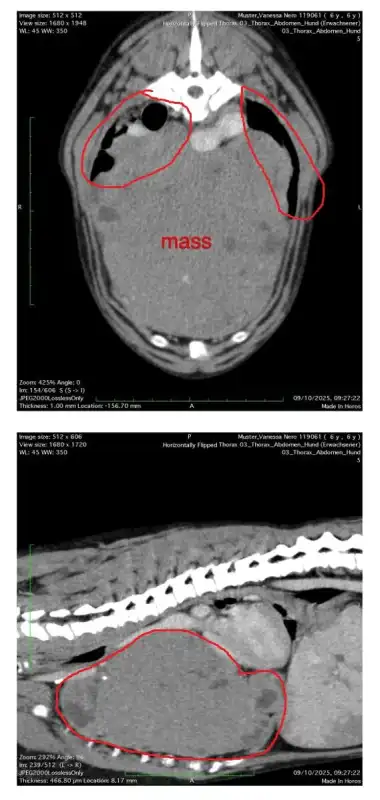

Jetzt steht er vor seiner größten Herausforderung: Ein sehr großer Tumor muss dringend operativ entfernt werden.

Der Tumor ist so groß, dass er bereits einen Großteil von Neros Lunge verdrängt hat. Ihm stehen nur noch ca. 20 % seiner Lungenkapazität zur Verfügung.

Dank seines unglaublichen Überlebenswillens konnte sich Nero an diese Einschränkung anpassen. Er ist ein Kämpfer und trotz seiner Atemnot rennt er noch über die Wiesen und spielt begeistert mit seinem Lieblingsstofftier. Aber die Zeit drängt.